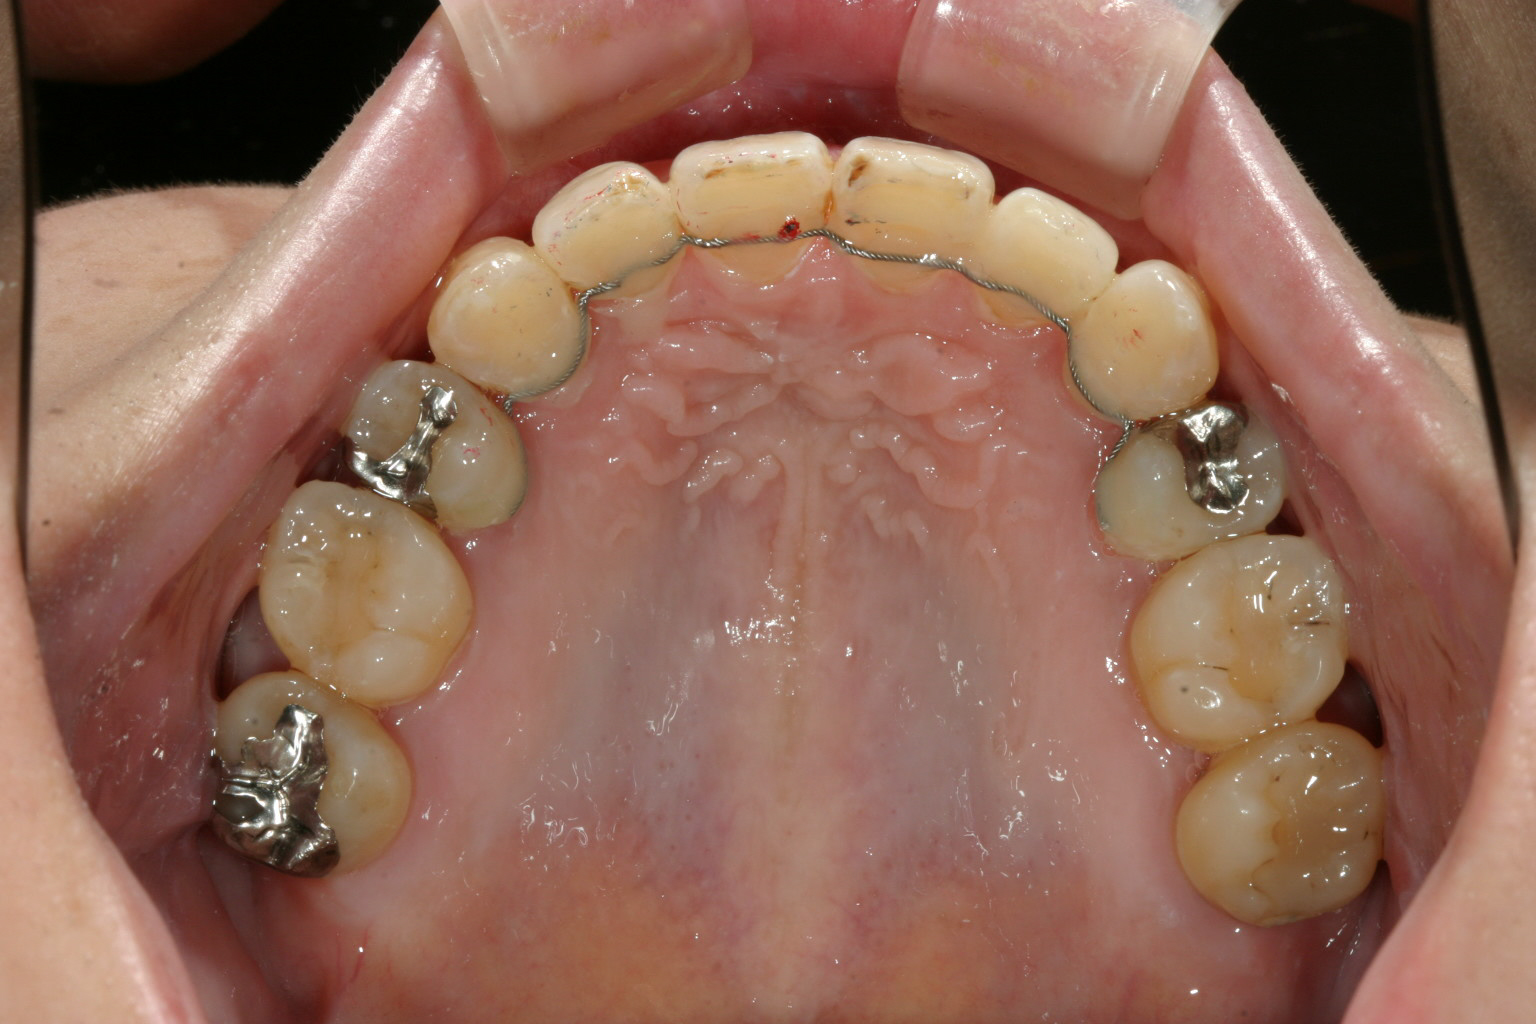

上顎左右小臼歯抜歯して治療致しました。

アーチは崩れ、犬歯は飛び出し、抜歯矯正となりなかなかインビザラインのマウスピースだけでは下に降りて来ずボタン貼ってアップダウンエラスティックかけたり、アーチの改善には写真は無いのですがクワッドヘリックス使い色々工夫しました。